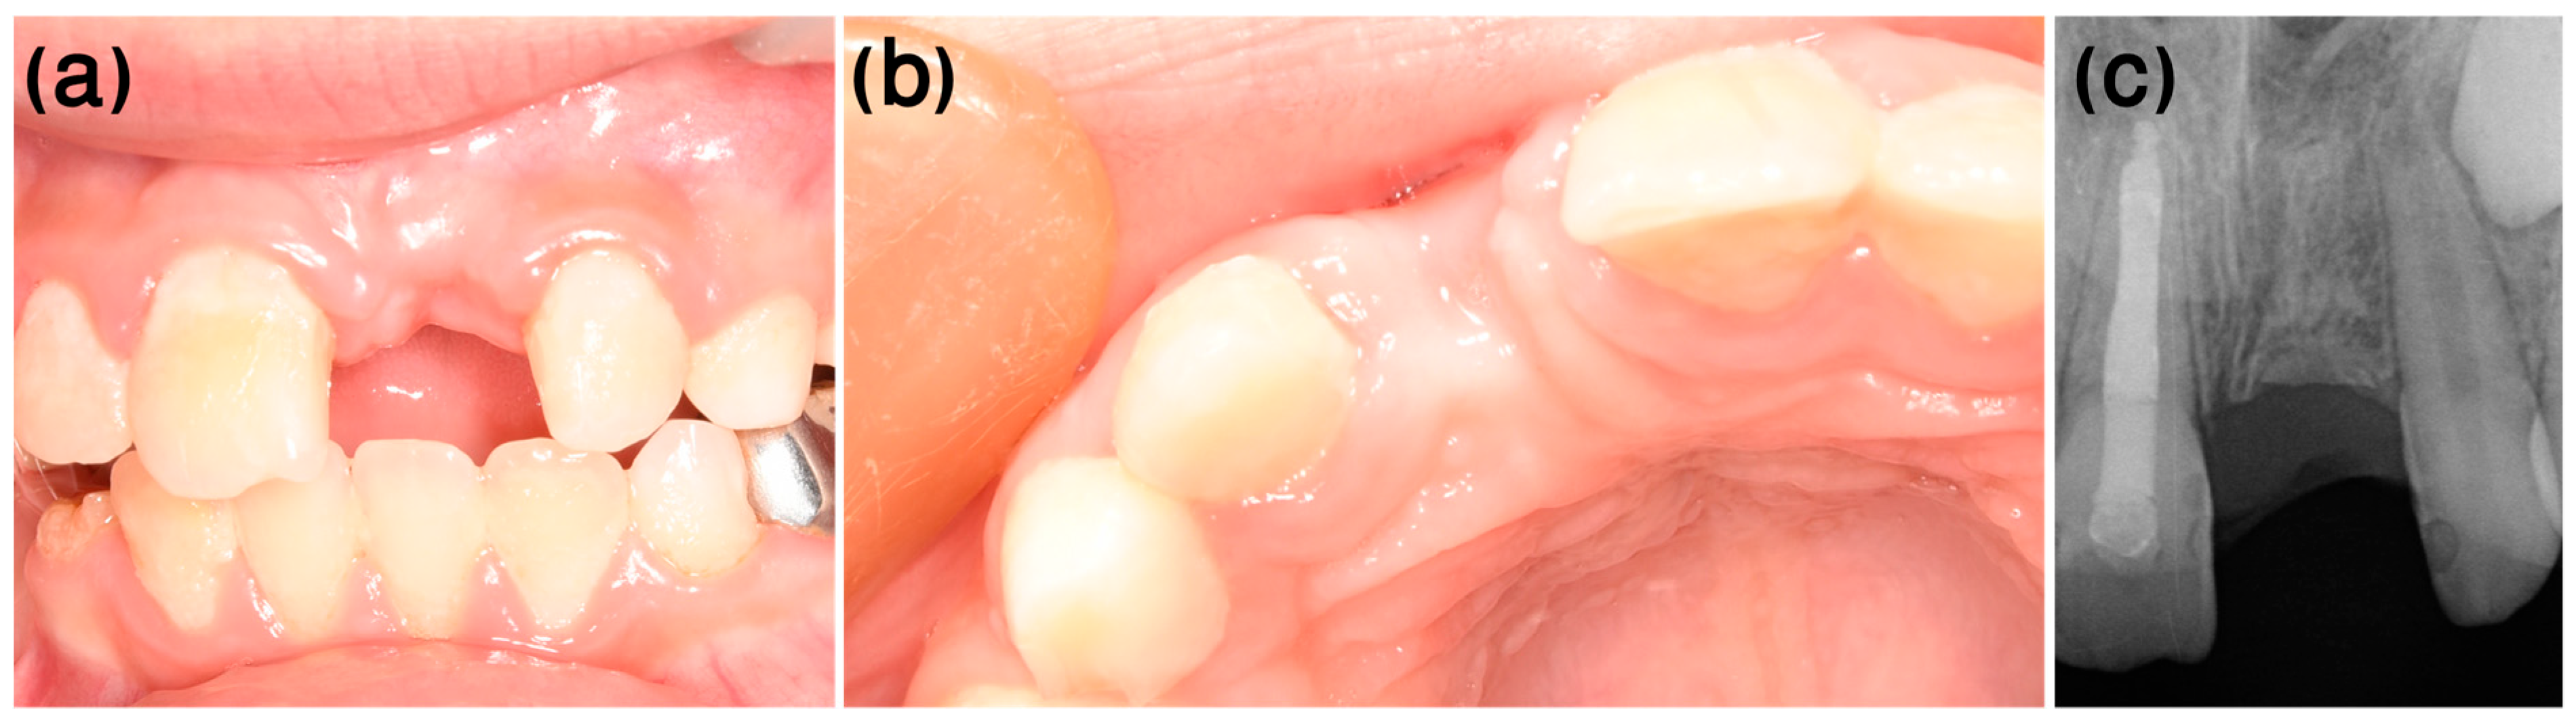

3.2. Case 2

- Dental history

- Clinical procedure

- Follow-up